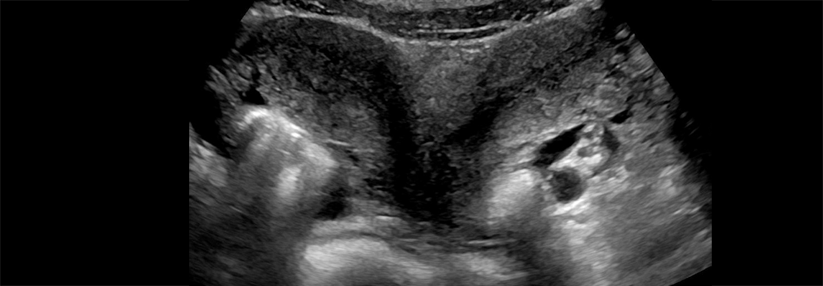

Damit Patienten mit einer Hormonstörung frühzeitig behandelt werden können, ist es wichtig, bei ihren Symptomen aufmerksam zu werden. Damit Patienten mit einer Hormonstörung frühzeitig behandelt werden können, ist es wichtig, bei ihren Symptomen aufmerksam zu werden. © wladimir1804 – stock.adobe.com

Damit Patientinnen und Patienten mit einer Hormonstörung frühzeitig behandelt werden können, sei es wichtig, bei Symptomen wie Stimmungsschwankungen, Gewichtszunahme, Müdigkeit oder Fruchtbarkeitsproblemen aufmerksam zu werden. Unter dem Hashtag #BecauseHormonesMatter will die DGE auf die Bedeutung der Hormone aufmerksam machen.